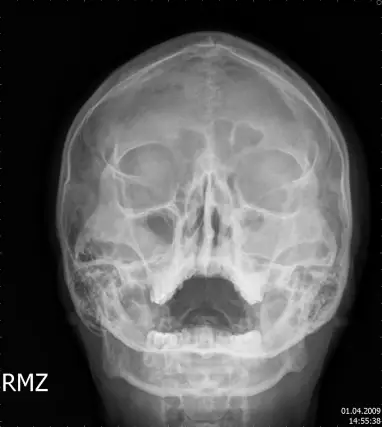

16歲男孩,主訴鼻塞、濃稠鼻涕已經超過一年。根據此張 X 光片,最可能的診斷是: 圖片描述

從提供的X光片(Occipitomental或Caldwell視圖)可見:

1. 雙側maxillary sinus腔內呈均質不透明影,輪廓平滑、邊界清楚,無明顯氣液面。

2. Ethmoid sinuses亦可見輕微黏膜增厚導致的淡淡不透明陰影。

3. 竇壁骨皮質完整,無非解剖線狀透亮影、無骨皮質缺損或移位、未見骨侵蝕或新骨形成。

上述影像符合慢性發炎所致黏膜增厚與竇腔不透明,而非創傷性骨折或腫瘤侵蝕。 (en.wikipedia.org)